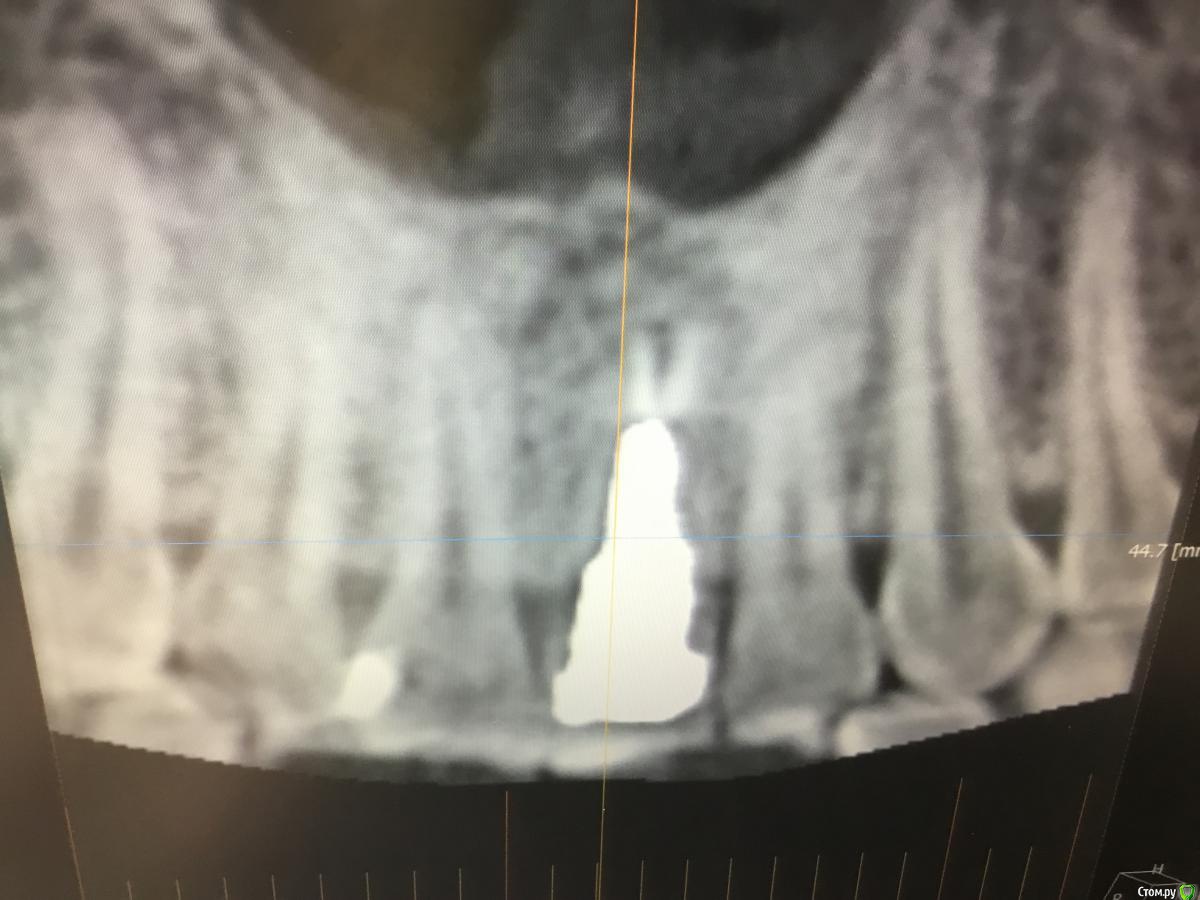

Zorrro Опубликовано 28 февраля, 2016 Поделиться Опубликовано 28 февраля, 2016 Пациента прислали на консультацию с кт. Огромная квк,ожидаемая трещина,локально гиперемия,подвижность коронки.Назначили аб терапию и записались на операцию через 2 дня.К сожалению нет фотодокументации с первой консультацией.Альтернативой немедленной нагрузки с костной и мягкотканной пластикой,были отсроченные костные блоки,с двухэтапным протоколом имплантации и тд и тп.С вероятным коллапсом мягких тканей,турбомобилизацией и прочими неприятными сопутствующими манипуляциями растянутыми по времени,а самое главное без ясного и прогнозируемого результата…короче решили рискнуть. Ссылка на комментарий

Zorrro Опубликовано 28 февраля, 2016 Автор Поделиться Опубликовано 28 февраля, 2016 А в реальности что с вестибулярного кортикакой? Её вообще нет?Вообще,то есть совсем. Ссылка на комментарий

Zorrro Опубликовано 29 февраля, 2016 Автор Поделиться Опубликовано 29 февраля, 2016 Кт после ещё нету,а качество его вполне хорошее (pointnix ).просто срезы кт в первом посте это фото экрана сделанное планшетом.в чём враньё не понял.? Ссылка на комментарий

Игорь Пеликан Опубликовано 29 февраля, 2016 Поделиться Опубликовано 29 февраля, 2016 (изменено) Вообще,то есть совсем. Если вестибулярной пластинки не бьіло,на кт похоже нет,и вьі засьіпали ету полость остепластом без ауто ,то ее и сейчас там нету,только мясо,из за етого и рецессия Изменено 29 февраля, 2016 пользователем Игорь Пеликан Ссылка на комментарий

Доктор Дмитрий Опубликовано 1 марта, 2016 Поделиться Опубликовано 1 марта, 2016 Кт после ещё нету,а качество его вполне хорошее (pointnix ).просто срезы кт в первом посте это фото экрана сделанное планшетом.в чём враньё не понял?У вас на кт нет вестибулярного кортикалки лунки Ссылка на комментарий

Zorrro Опубликовано 1 марта, 2016 Автор Поделиться Опубликовано 1 марта, 2016 А хотелось бы чтобы клиническая картина соответствовала рентгенологическое, вы ведь говорите что кортикалка была.Перечитайте,пожалуйста,где я написал,что кортикалка есть?Наоборот писал,что в проекции 21 её нету,на кт её тоже нету.во время операции тоже не заметил.может вы неправильно меня поняли или я что-то не так написал? Ссылка на комментарий